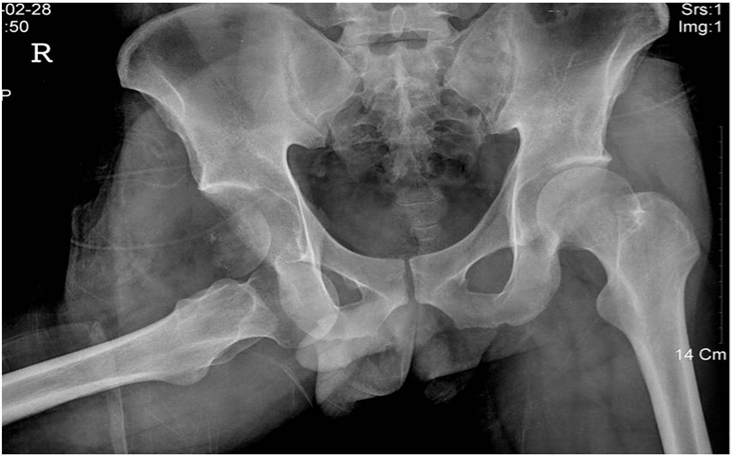

A 27-year-old man was injured by automobile accident and immediately presented to our emergency department. On physical examination, right hip was in flexion, external rotation and abduction. He complained of severe pain, and passive and active movements were not possible in right hip. There was neither neurovascular deficiency nor associated injuries. Radiograph of both hip revealed obturator dislocation of right femoral head and fractured femoral head fragment within hip joint (Figure 1). The dislocation was immediately reduced by traction in line of deformity followed by gentle adduction and internal rotation with pelvis stabilized by an assistant. After closed reduction, anteroposterior radiograph showed femoral head was reduced but crescentic radio-opacity was visible overlying femoral head and translateral radiograph revealed that the fractured femoral head fragment was turned inside out during closed reduction (Figure 2A & 2B). Computed tomogram depicted the 3-D configuration of fracture (Figure 2C & 2D).